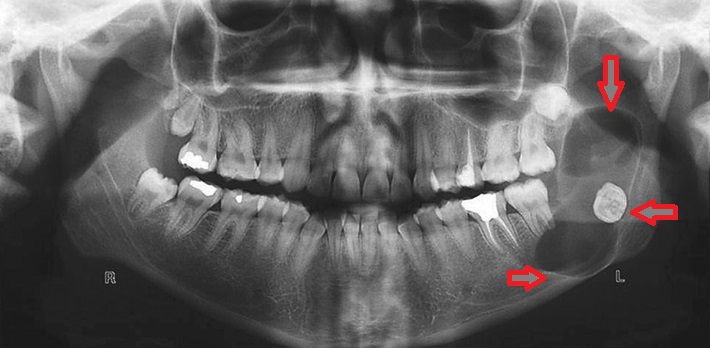

Normal halda insanın diş sırasında hər çənədə iki ədəd olmaqla, ümumilikdə dörd agıl dişi mövcuddur. Ağıl dişinin çıxması bəzi şəxslərdə heç bir kliniki əlamət və ya şikayətə səbəb olmasa da, bir çox hallarda müəyyən kliniki əlamətlərlə öyünü biruzə verir. Bu əlamətlər əsasən çənənin arxa tərəfində təzyiq, çənəni açıb baglama əsnasında agrı və məhdudlaşma kimi özünü göstərə bilir. Bu hallarda mütəxəssis konsultasiyasının önəmi olduqca böyükdür. Belə ki müayinə zamanı cərrah-stomatoloq kliniki və radioloji dəyərləndirmə apararaq dişin dogru pozisiyada yerləşib yerləşmədiyi, dişləmə çıxma ehtimalını, agıl dişinin çənəyə görə ölçüsü və çənə darlıgı kimi durumları dəyərləndirərək tətbiq edilməli olan müalicə taktikasını müəyyən edir.

- Retensiyon ağıl dişinin spontan və ya ortodontik olaraq dişləmə çıxma ehtimalı mövcud deyilsə

- Ağıl dişinin ətrafında iltihabi proses və ya xoş/bədxassəli törəmə mövcuddursa və prosesin müalicəsi ağıl dişinin çəkilməsini tələb edirsə

- Ağıl dişi qonşu dişdə karies, sorulma, parodontal problemlər və s. yaradırsa